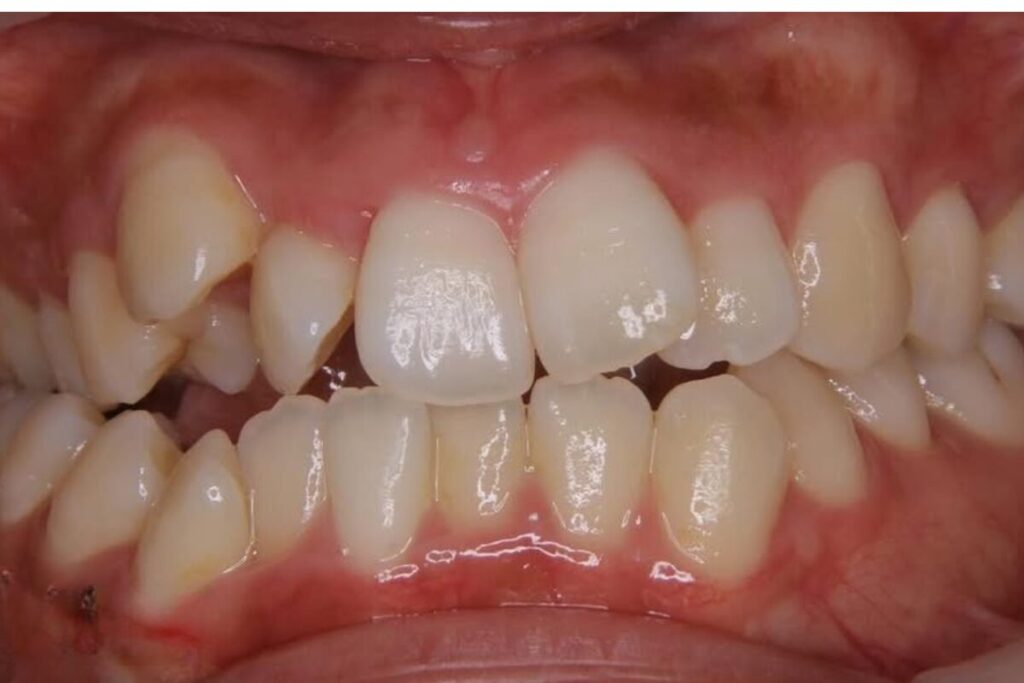

| 患者 | 28歳男性 |

|---|---|

| 主訴 | 歯ならびのガタガタ |

| 診断名 | UR7/LR7クロスバイトと上下叢生を伴うAngleⅠ級sk.1不正咬合 |

| 治療内容 | マウスピース型矯正装置(インビザライン)、部分的に上顎前歯部にワイヤー併用 |

| 抜歯の有無 | 非抜歯 |

| 治療期間 | 2年 |

| 費用(税込) | 594,000円 |

| リスクと副作用 | 痛み等、歯根吸収/歯肉退縮、後戻り、むし歯・歯肉炎の可能性。 |

【医師コメント】

上下のガタつきで来院された患者さんです。

精密検査の結果、UR7/LR7のクロスバイト(交叉咬合)と上下の叢生を伴う AngleⅠ級(sk.1)不正咬合 と診断しました。奥歯の前後関係はⅠ級で大きなズレは強くない一方、奥歯の噛み合わせのズレとスペース不足が原因でした。

治療はインビザラインを主体に非抜歯で計画し、歯列全体のバランスとかみ合わせの安定を意識しながら段階的に改善を進めました。

終盤、UL2のローテーションがわずかに残ったため、仕上げの精度を高める目的で上顎前歯部に部分的にワイヤーを併用しています。

治療は計画に沿って進行し、2年で歯列の配列とかみ合わせの改善を図ることができました。